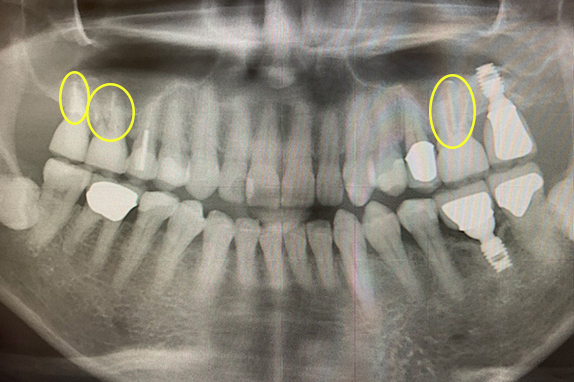

CASE 02 マイクロエンド(精密根管治療)+歯周基本治療

-

- 主訴

- 右も左も痛くて噛めない(60代女性)

-

- 回数期間

- 15回 約6ヶ月

-

- 治療法

- マイクロエンド(精密根管治療)+歯周基本治療

-

- 治療費用

- 約60万円(税抜)

右も左も痛くて噛めないという主訴で来院。マイクロエンドをし歯周基本治療で改善したケースです。

<リスク・副作用>

治療後は痛み、腫れ、痺れなどの副作用が生じる場合があります。症状が再発する可能性があります。